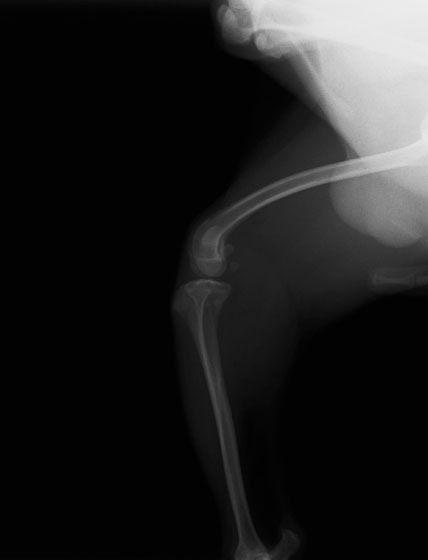

■ 症例24 キャバリア 7か月

左右膝蓋骨内方脱臼(左:グレードⅣ 右:グレードⅢ)

以前から左右後肢の跛行が認められ、整形外科学的検査・レントゲン検査により左右の膝蓋骨脱臼が認められた。症状が重度である左膝の膝蓋骨脱臼整復術を行った。外科手技は縫工筋及び内側広筋の解放、脛骨粗面の外側転位、滑車ブロック形造溝術、内外側関節方の縫縮を実施した。術後一か月時点で、左の膝蓋骨は安定しており経過は良好である。

本症例は成長期における重度の膝蓋骨脱臼であり、術後の再発の可能性もあるため、経過をしっかりと観察していく必要がある。また、今回手術を実施していない右膝に関しても経過を観察し、手術を検討していくこととする。